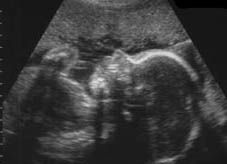

Фотохроника развития плода

Личико 28-недельного плода